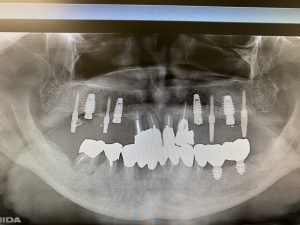

(After)

抜歯即時埋入(抜歯と同時にインプラント埋入手術を行う)さらに、同日に直ぐに噛めるように暫間的なインプラントまでも入れる手技、、

抜歯と同時にインプラントを埋入する手技は患者さんにとっては『オペ』が一度で済む利点がありますが術者の高いスキルが要求されるオペです。今回はさらに患者さんの食と生活の質(Q.O.L)を落とさず日常生活を過ごして頂く為に補助的インプラントを同時に埋入し『噛めないなら→噛める』場所を仮にでも作ろう!(CT解析後にガイドプレートなどに頼るオペは時にブレがあり現場で使えない事しばしば)(理事長のオペはそれらを踏まえて先の先を見越し事前の解剖学的組織や形態を頭と腕に叩き込みフリーハンドで施術します)

※ちなみに暫間インプラントは本インプラントが生着する概ね2〜3ヶ月位で撤去します